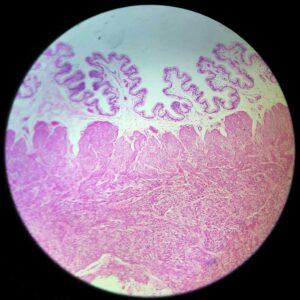

Human Spleen Section

Thickness: 7-micrometer section

Stain: hematoxylin and eosin

Scientific name: Human spleen section

Description of the Human spleen section:

- Size: 76.2*25.4mm

- Thickness: 7-micrometer section

- Stain: hematoxylin and eosin

- Show: red pulp, splenic nodule, central artery